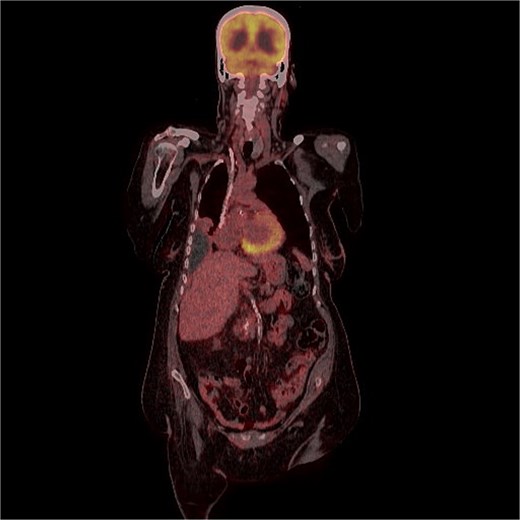

A 70-years old female came to the tertiary hospital, with a gradually enlarging right frontal-temporal scalp swelling associated with headache. She presented to the ER with abnormal movement, described by the son was gazing upward toward specific point with right upper limb jerky movement lasting for 15 s and frothy secretions, not responding during the event. Whole event lasted for 40–45 s. No reported pre-event symptoms and for post event patient was back to baseline after one-to-one hour and half. The son noticed this event repetitively happens on exertion, positioning the patient from lying to siting position, and before the dialysis sessions. Regarding her surgical and medical history, she is a known case of type 2 diabetes mellitus, hypertension, end-stage renal disease on dialysis, and cardiac disease with low ejection fraction. In addition, the patient had undergone a total abdominal hysterectomy with bilateral salpingo-oophorectomy under spinal anaesthesia in for endometria carcinoma, stage IB, grade 2 and subsequently received vaginal vault brachytherapy. Upon physical examination, the patient was noted to have a large, non-tender, soft to firm swelling in the right frontal-temporal region, with no other remarkable findings. CT with contrast (Figs 1 and 2) of the brain revealed metastasis to the right frontal bone and the greater wing of the sphenoid, with large extra-cranial and small intracranial soft tissue components with no parenchymal brain lesions were observed. A brain biopsy confirmed that there was fibromuscular and adipose tissue with focal necrosis and atypical cells, with crushed and scarse atypical cells likely neoplastic or reactive. Also, PET CT scan (Figs 3 and 4) confirms that there was brain metastasis sparing lymph nodes. Given her poor status and significant comorbidities, she was deemed unfit for systemic chemotherapy. The patient received palliative radiotherapy to the scalp lesion 20 Gy in 5 fractions.

FDG uptake was noted in the scalp lesion, while no other areas of abnormal uptake were identified elsewhere.